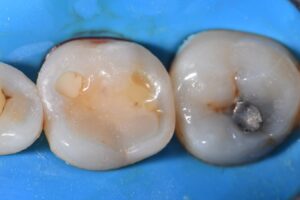

Home/Blog / Cavities between the teeth

#KerrSimplishadeMedium #ClassIICloudComposites